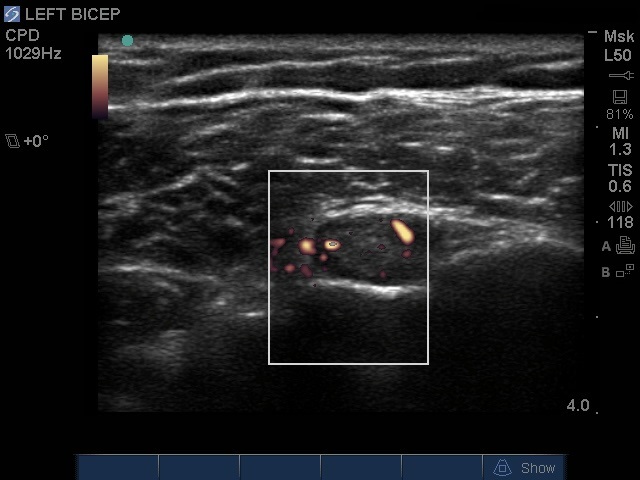

Image - Épaule : Ténosynovite du biceps, coupe petit axe en Doppler puissance